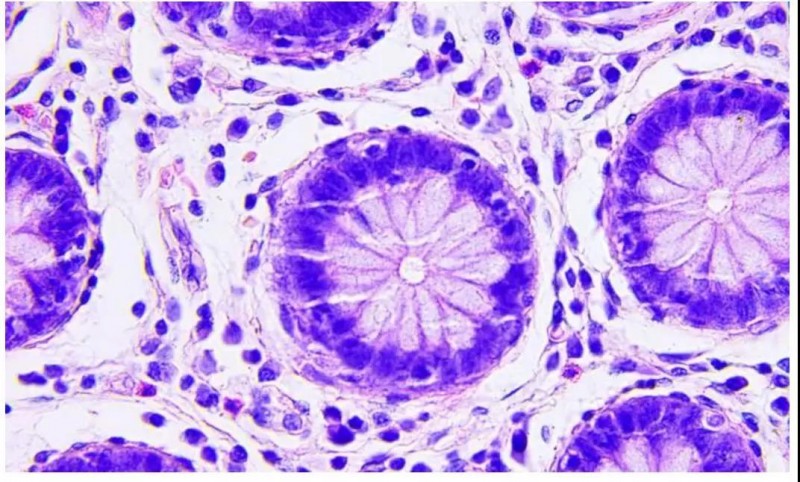

结直肠癌是全球第三大常见癌症,也是癌症相关死亡的第三大原因。结直肠癌患者死亡的主要原因是肝转移,近70%的患者最终发展为肝癌。最近的研究揭示了人类结直肠癌细胞中的低水平蛋白激酶Cζ(PKCζ)的肿瘤抑制因子与远处转移的关系,但尚不清楚这如何影响肿瘤的扩散和患者的不良预后。

一项新研究有助于解释PKCζ与转移性结直肠癌之间的关系,发表在Cell Reports上,描述了PKC zeta缺陷如何通过失去一种叫做ADAR2的酶促进肝转移,并随后从癌细胞向血液中分泌miR-200s的分子。另外,用抑制miR-200分泌的化合物治疗可显着降低结直肠癌小鼠的肝转移。

研究结果表明血液中miR-200水平升高可以作为有转移危险的患者的非侵入性诊断标记物,这项研究具有巨大的潜在治疗相关性,因为它提供了一种概念,即靶向PKC zeta缺失所激活的信号可能是有用的抗转移疗法。

总而言之,这里报道的结果突出显示了识别信号的重要性,释放肿瘤抑制因子的失活和建立PKC zeta衍生的信号,控制miR-200s作为癌症转移中潜在的重要治疗靶点。在未来的研究中,研究人员将通过研究ADAR2如何调控miR-200s的分泌来解决这个问题。癌症转移占所有癌症相关死亡的90%以上,确定调节多种类型肿瘤扩散的治疗靶点会对患者的生存产生巨大影响。